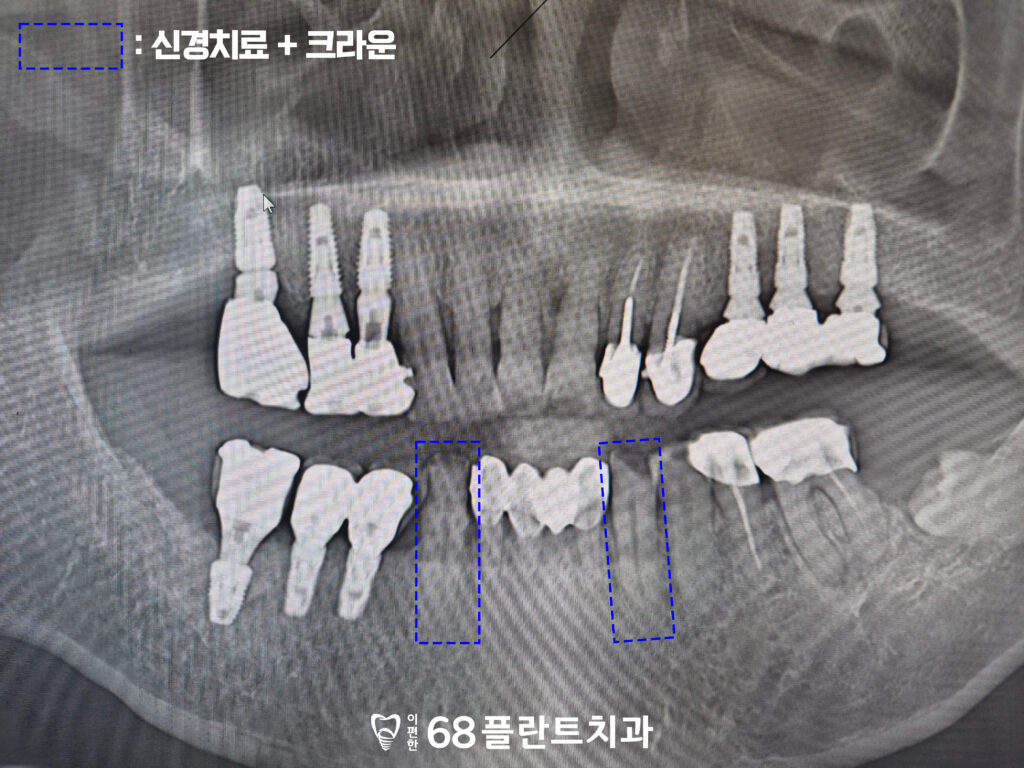

위 환자분은

전체적으로 치아가 안 좋은 거 같다며

철산역치과 이편한68플란트에

내원해 주셨습니다.

확인해 보니,

치주질환으로 인해

잇몸뼈가 소실되어 흔들리고

뿌리가 드러난 치아도 있었는데요.

해당 치아들은 살려서 쓴다고 해도

예후가 좋지 않아

장기적으로 안정적인 기능을

기대하기 어려운 상황이었습니다.

따라서, 발치와

임플란트 치료가 필요했습니다.

또한 기존 임플란트를

보철물들의 마모나

손상이 보였습니다.

이로 인해 임플란트의

기능이 저하되고,

미적 측면에서도 문제가

발생할 수 있었습니다.

따라서, 기존 보철물의 상태를 고려해

재보철이 필요했습니다.

아래 송곳니는 발치 없이

신경치료와 크라운으로

보존할 수 있다고 진단을 내렸습니다.